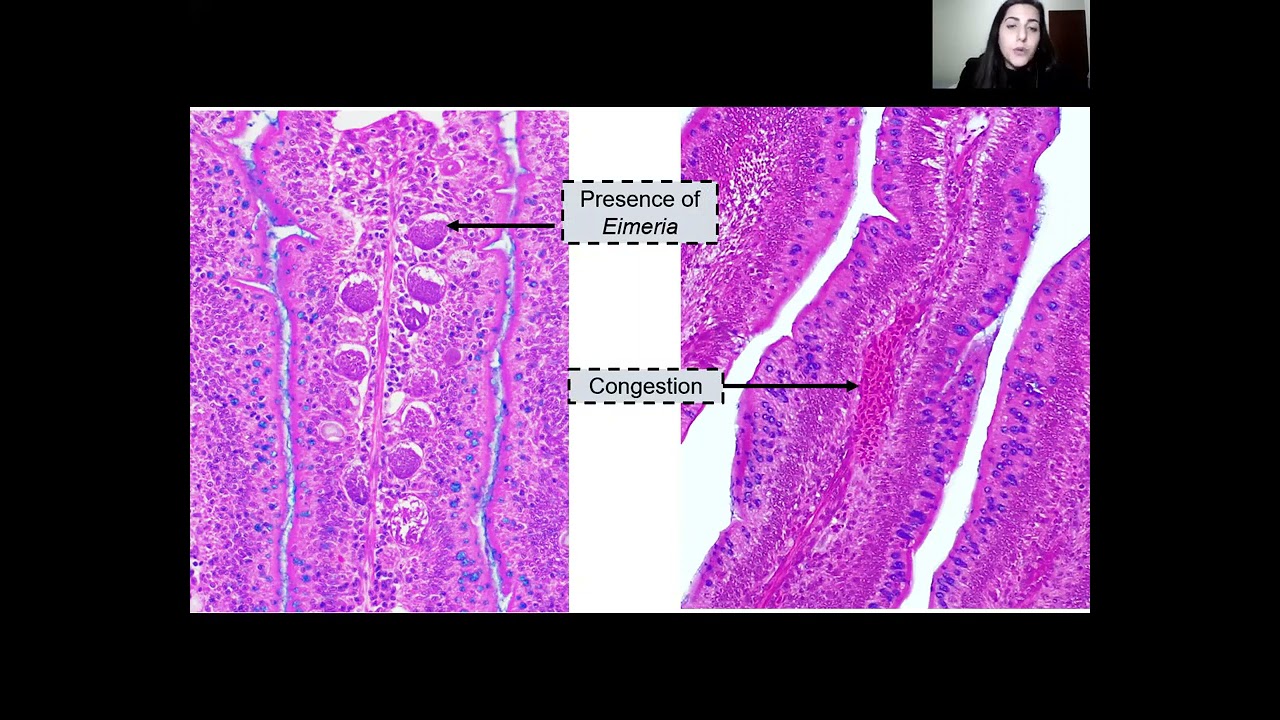

Day 4   PM Sessions   Understanding and Combating Mycotoxins for Sustainable Poultry Production

Day 3   PM Sessions   Immune Response to Coccidiosis in Poultry